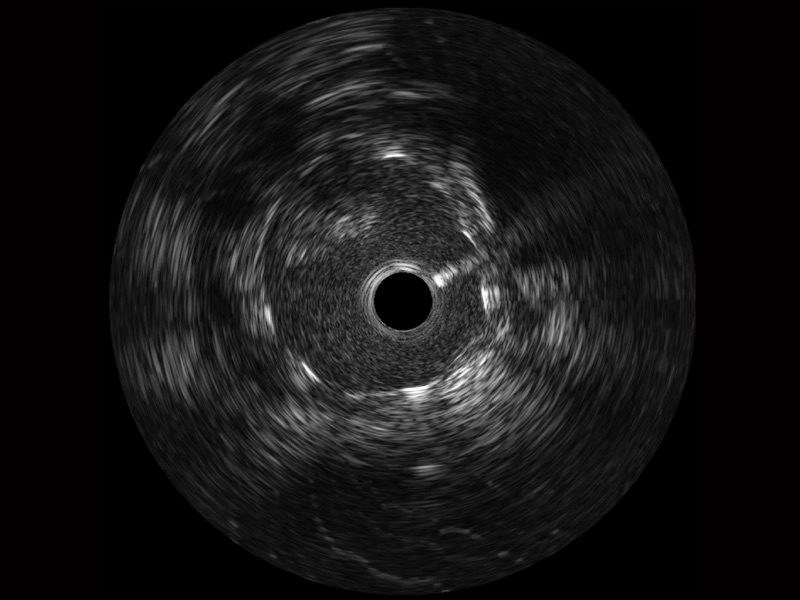

• 亚星官网宽频IVUS图像

• 传统IVUS图像

对比传统IVUS导管成像,亚星官网宽频IVUS图像的近场支架梁显影更细腻,远场中膜外血管仍清晰可辨,兼顾远中近,兼顾分辨力与穿透深度